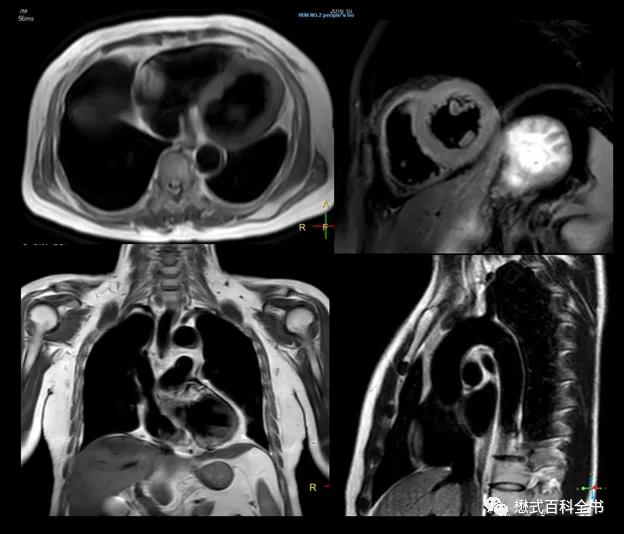

所谓的双反转黑血序列,就是在采集信号之前,首先施加了两个反转脉冲,将磁化矢量从纵向翻转到负方向。这个技术一般会和心电同步技术联用。当检测到QRS波时,首先施加第一个反转脉冲,这个反转脉冲是非层面选择的180°脉冲,将所有组织的磁化矢量都反转到-Z。接着一瞬间立马施加第二个反转脉冲,这个反转脉冲是层面选择的180°反转脉冲,只有被选择的层面反转180°,等于返回原来状态。也就是说,通过连续两个反转脉冲,成像层面的组织磁化矢量是在正方向,而成像层面以外的所有组织磁化矢量是在负方向。被反转到负方向的组织会进行纵向驰豫,逐渐向正方向恢复。当血液组织的磁化矢量刚好过零点时,这个时间施加90°射频脉冲,则血液组织信号被抑制,也就是层面外的所有血液组织信号被抑制掉。而层面内的血液由于信号流空也不会产生信号,并且层面外血液信号被抑制,即使流入采集层面也不产生信号,所以整个血液信号被抑制。

这种序列其实就是在快速自旋回波序列之前施加了连续两个反转脉冲,两个反转脉冲可以看作是为了形成黑血效果而做的准备脉冲阶段,而后面的快速自旋回波则是信号采集阶段。有了这个双反转脉冲,就可以保证无论是层面内,还是层面间的血液信号都被抑制。即使有血液在这个过程中,流出再流入采集层面,也不胡产生信号,保证了黑血效果的稳定性。